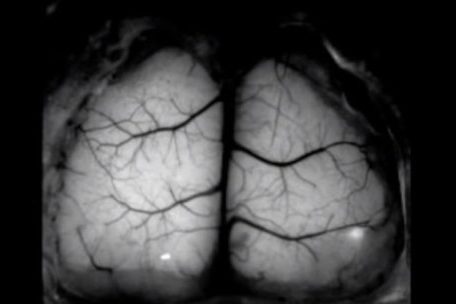

- 5 Ученые создали прозрачный имплантат для изучения живого мозга в реальном времени